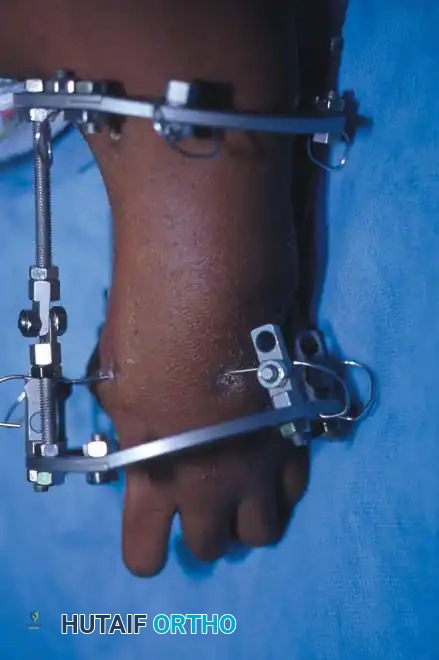

Surgical Interventions in Transverse Deficiencies

Surgical indications for transverse deficiencies are exceedingly rare. Epps, Burkhalter, and McCollough reported that out of 1,077 children